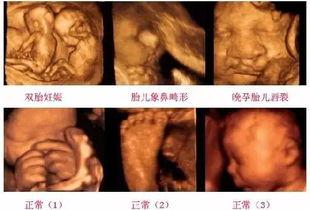

首先得说,德国产检B超视频的画质真的是没得挑。高清的画质让每一个细节都清晰可见,宝宝的小手、小脚、小脸蛋,还有那些血管、器官,都仿佛就在眼前。这种画质让人仿佛能感受到宝宝在妈妈肚子里的呼吸和心跳,真是太神奇了!

德国的产检医生都是经过严格培训的,他们不仅技术高超,而且经验丰富。在B超视频里,我们可以看到医生们认真观察每一个细节,对宝宝的发育情况进行精准诊断。从胎位、胎心到羊水量,甚至是宝宝的性别,医生们都能准确判断。这种专业程度让人不得不佩服德国的医疗水平。